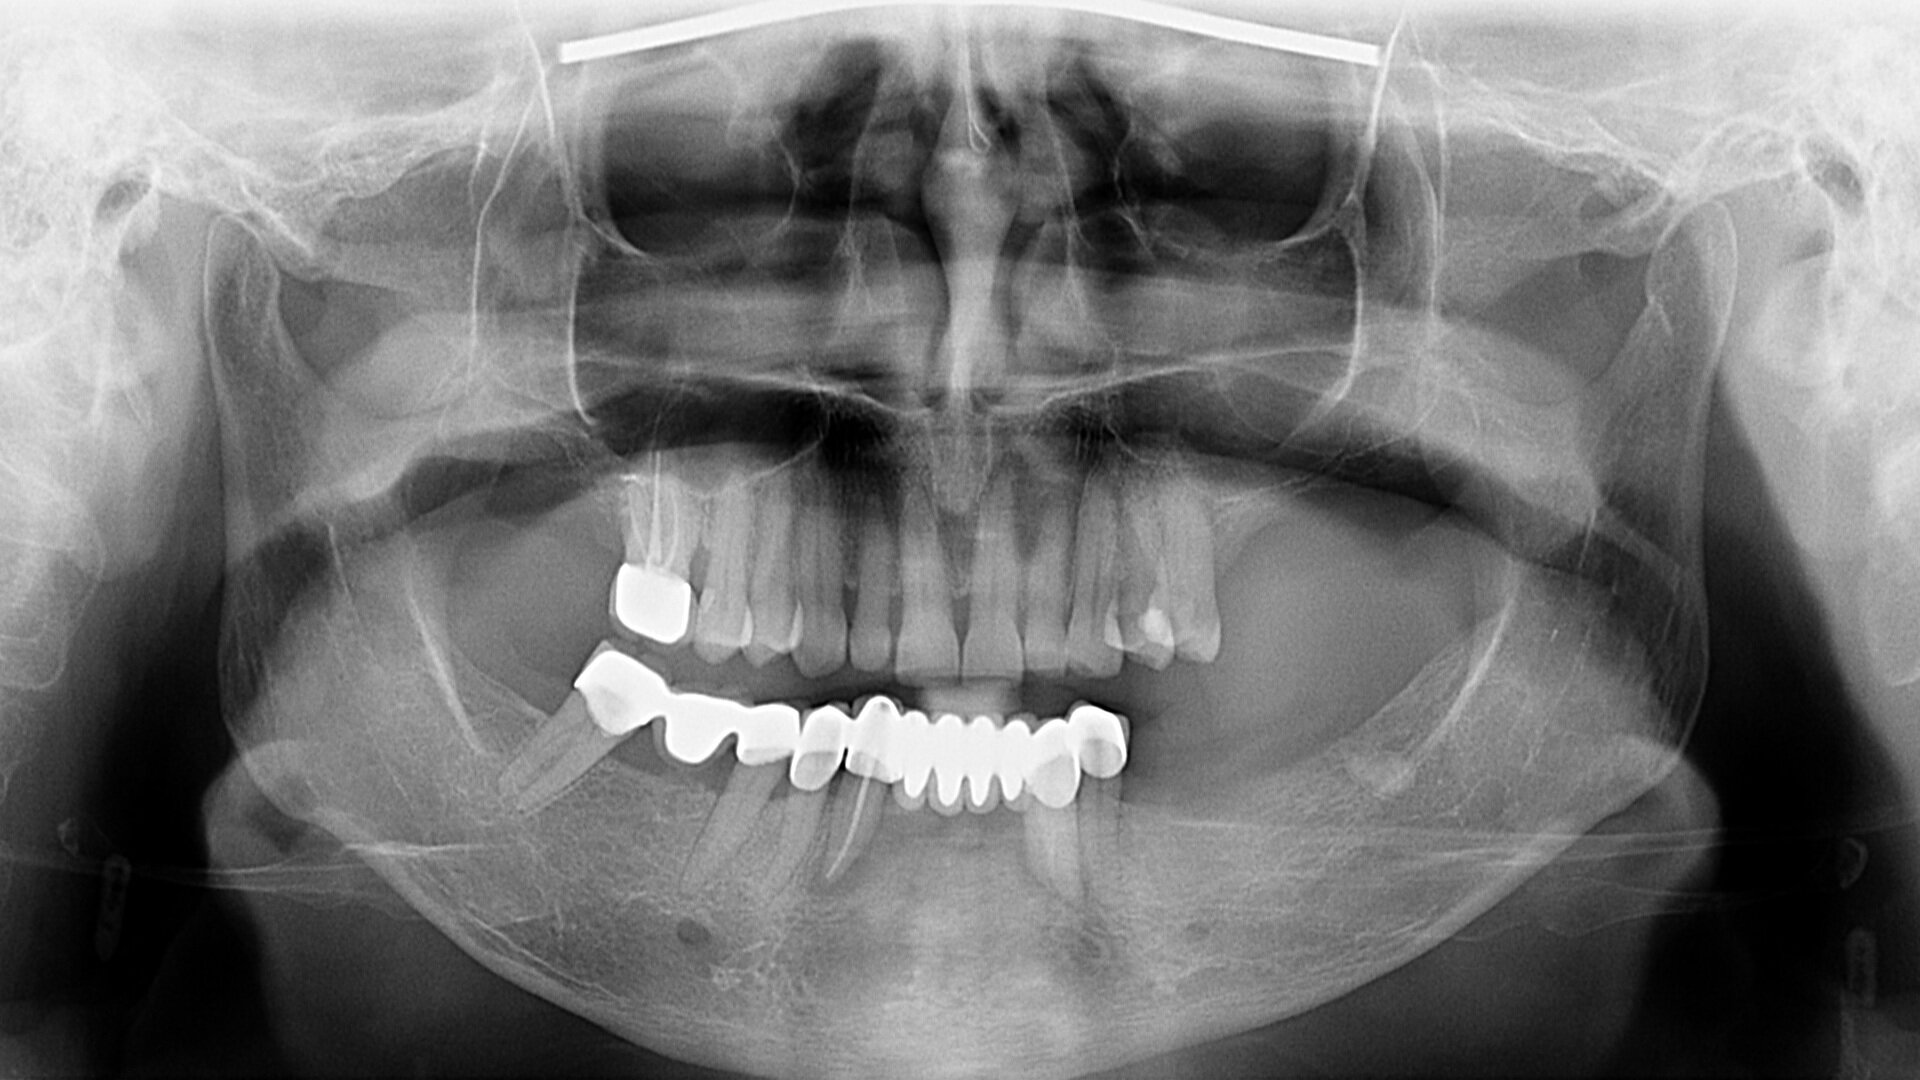

Figs. 2a & b: Intra-oral scans of the pre-op situation.

Intra-oral examination revealed compromised mandibular dentition, an old fixed prothesis, missing posterior teeth on the left side, periodontal involvement and gingival inflammation. A panoramic radiograph was obtained, and the findings were reported to the patient (Figs. 1a & b; 2a & b). Both mandibular canines had visible periapical radiolucencies. A CBCT scan was performed for a more detailed assessment of the alveolar bone anatomy (Figs. 3a & b). Temporomandibular joint examination revealed no indication of dysfunction (crepitus, clicking or pain).